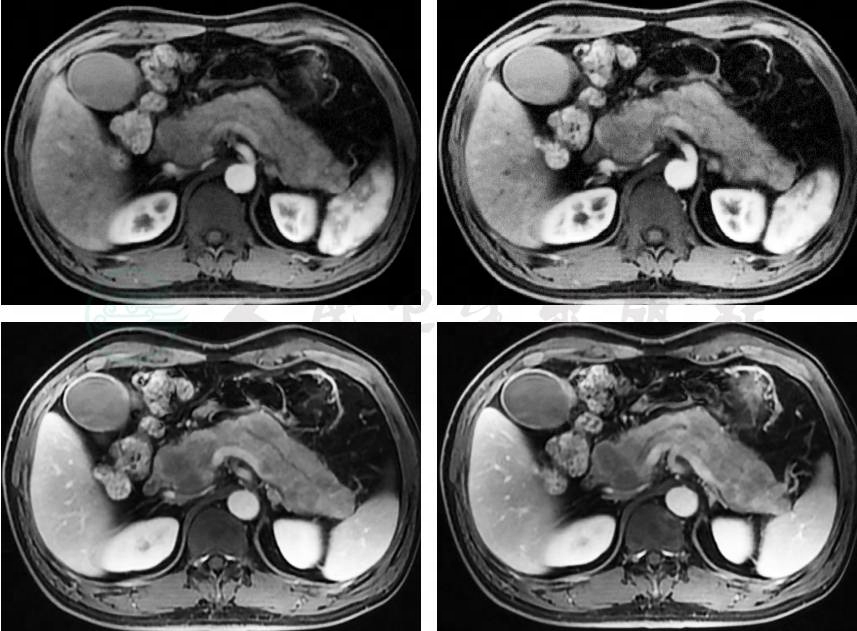

2019-12-15:胰腺磁共振(magnetic resonance,MR)平扫+增强(图4)示①胰腺异常改变,考虑急性坏死性胰腺炎可能性大,待结合临床诊断;②胰管轻度扩张;③扫及脂肪肝,肝内外胆管轻度扩张;④急性胆囊炎,胆囊少许沙砾样结石可能性大;⑤腹膜后、门腔间隙多发轻度肿大淋巴结。

图4 胰腺MR平扫+增强(2019-12-15)